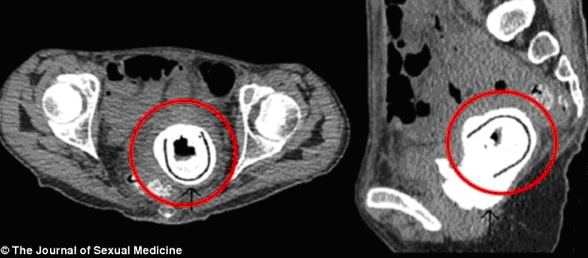

Mắc dị vật trong cơ thể: Bệnh viện Hoàng gia Aberdeen, Scotland đã tiếp nhận ca mắc kẹt dị vật trong cơ thể vô cùng hy hữu của một nữ bệnh nhân 38 tuổi. Một món đồ chơi tình dục có chiều dài tới 11 cm nằm trong âm đạo của cô suốt 10 năm mà cô không hề hay biết.

Chỉ sau khi xuất hiện những triệu chứng bao gồm sút cân nghiêm trọng, rùng mình hay hôn mê, người phụ nữ này mới tới bệnh viện khám. Các bác sĩ đã phát hiện và phẫu thuật lấy ra một món đồ chơi tình dục có chiều dài 11 cm từ âm đạo của cô. Các bác sĩ cho biết, đây là trường hợp đầu tiên mà đồ chơi tình dục lại mắc kẹt trong âm đạo của phụ nữ trong khoảng thời gian dài tới như vậy.

Mắc kẹt đồ chơi tình dục trong cơ thể mang lại hậu họa khôn lường |